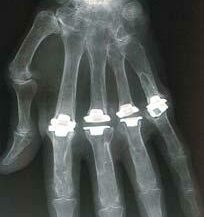

Prothèses articulaires interphalangiennes

Les prothèses articulaires interphalangiennes sont des dispositifs médicaux utilisés pour remplacer une ou plusieurs articulations interphalangiennes (IP) dans les doigts des mains. Ces prothèses sont généralement utilisées lorsque l’articulation est gravement endommagée par l’arthrose, les traumatismes ou d’autres affections qui affectent la fonction de l’articulation. L’objectif de l’implantation de ces prothèses est d’améliorer la mobilité, de soulager la douleur et d’augmenter la fonctionnalité du doigt.